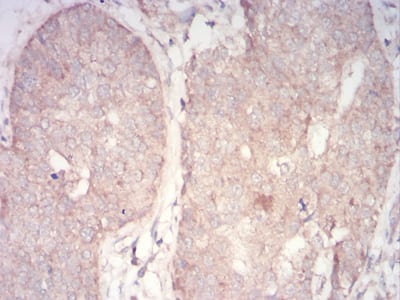

Immunohistochemical analysis of paraffin-embedded human bladder cancer tissues using PDPK1 mouse mAb with DAB staining.